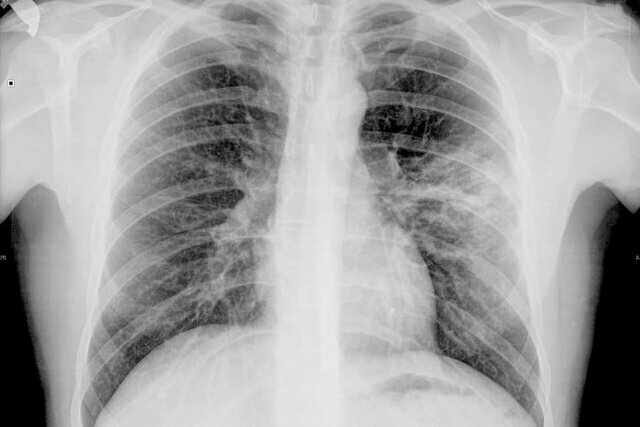

La neumonía atípica es un tipo de neumonía generalmente adquirida en la comunidad causada por distintos a los tradicionales. Se caracteriza por síntomas respiratorios predominantes y que pueden incluir cafalea, fiebre poco elevada, tos, malestar general y artromialgias.